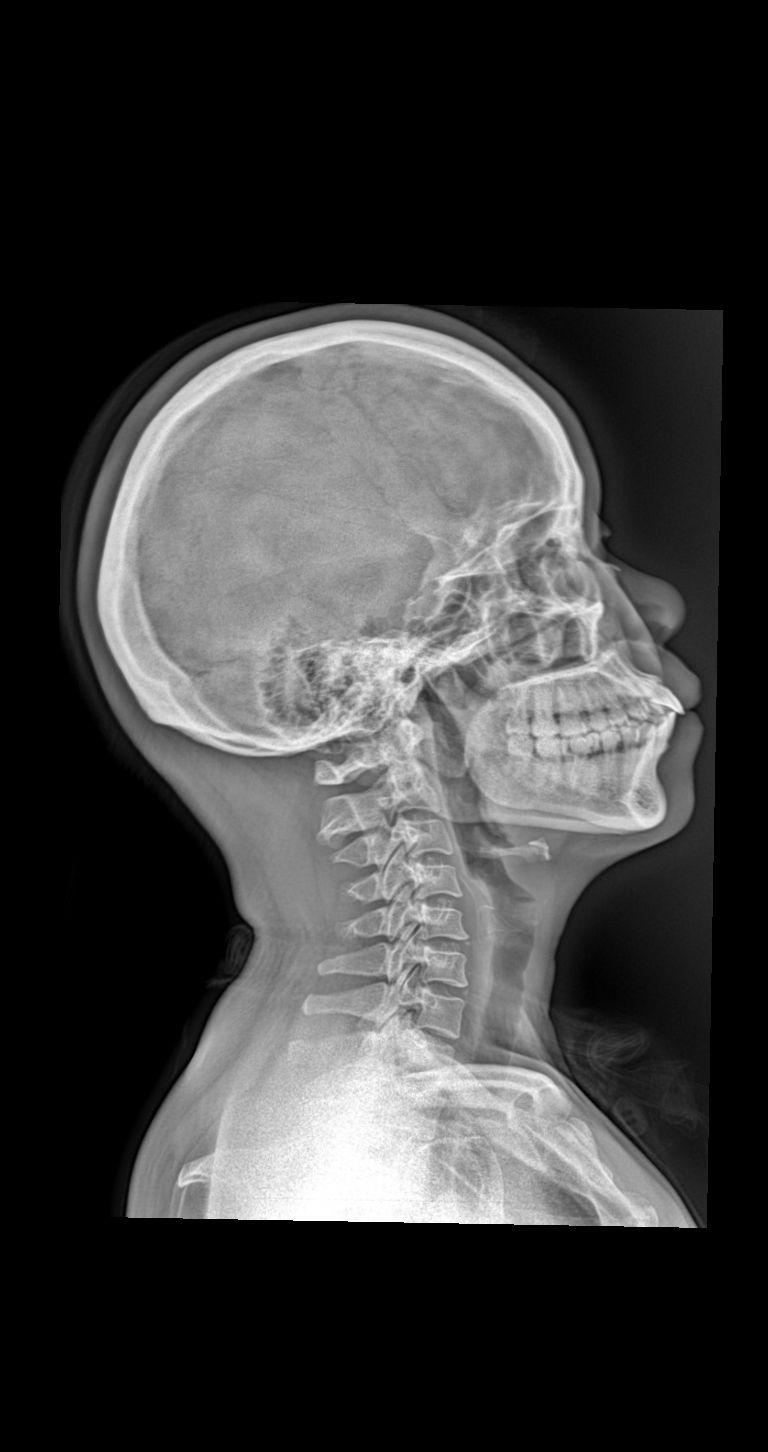

颈部疼痛 头晕 就诊